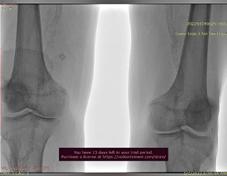

O altă complicaţie a diabetului zaharat asociată cu un grad semnificativ de morbiditate este boala arterială periferică, pacienţii diabetici prezentând mult mai precoce stenoze carotidiene semnificative sau ischemie cronică de membre inferioare complicată cu ulceraţii sau gangrenă care necesită o abordare multidisciplinară cu departamentele de chirurgie vasculară sau cardiologie intervenţională pentru salvarea membrelor. Oportunităţile de revascularizare sunt adesea reduse la pacienţii diabetici datorită leziunilor multiple și distale faţă de cazurile care nu asociază diabet. Investigaţiile bolii arteriale periferice cuprind indicele gleznă-braţ și haluce-braţ, ecografia Doppler și angiografia intervenţională, prin computer tomograf sau rezonanţă magnetică și calcularea scorului ’’WifI’’ pentru evaluarea riscului de amputaţie. Pe lângă soluţiile de revascularizare chirurgicală sau prin angioplastie percutană transluminală, pacienţii cu boală arterială periferică cronică simptomatică fără risc de sângerare înalt beneficiază de tratament cu Rivaroxaban în doză mică (2.5mg de 2 ori pe zi) și acid acetilsalicilic.